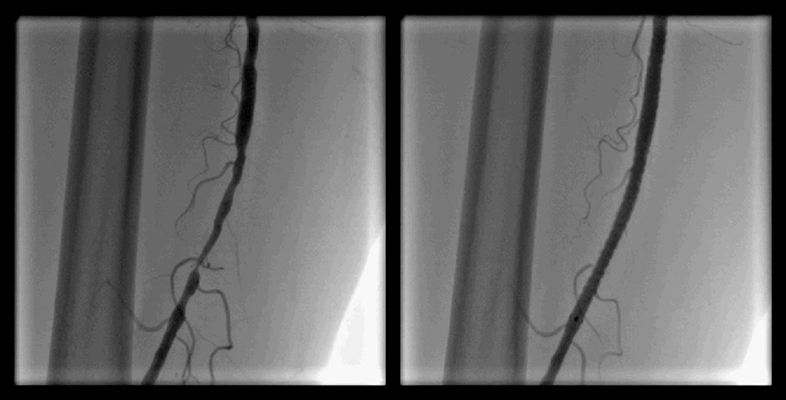

ガイドワイヤー通過

![]()

バルーン拡張

ステント留置

血管内手術

- 浅大腿動脈狭窄 【写真】

- 浅大腿動脈閉塞 【写真】